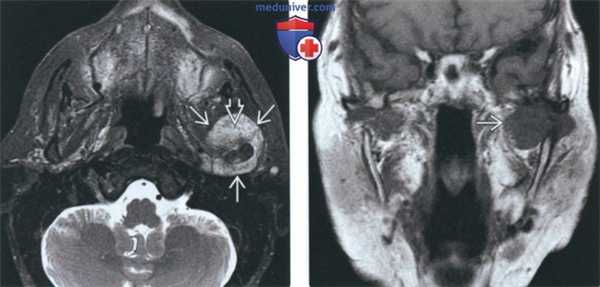

(а) Женщина 77 лет с жалобами на боли в груди, усиливавшиеся в течение шести месяцев.

При нативной КТ в латеральных отделах 6-го ребра справа определяется объемное образование размером 5 см с хондроидной структурой. При резекции данного образования была выявлена хондросаркома грудной стенки.

(б) Мужчина 56 лет с жалобами на боли в груди и пальпируемое объемное образование на передней грудной стенке. При нативной КТ в грудине визуализируется объемное образование с мягкотканным и хондроидным компонентами.

Данная картина позволяет заподозрить первичную хондросаркому грудной стенки.

(а) Женщина 32 лет с болезненным объемным образованием на передней грудной стенке.

При нативной КТ (костный режим) определяется деструкция грудины за счет объемного образования с хондроидной структурой (множественные кольцевидные, дугообразные и точечные кальцификаты).

(б) У этой же пациентки при остеосцинтиграфии в косой проекции в рукоятке грудины визуализируется участок выраженного накопления Тс-99m-МДФ.

Для хондросарком грудной стенки типична локализация в грудине и реберных хрящах. При остеосцинтиграфии данные опухоли обычно характеризуются повышенным уровнем накопления РФП.